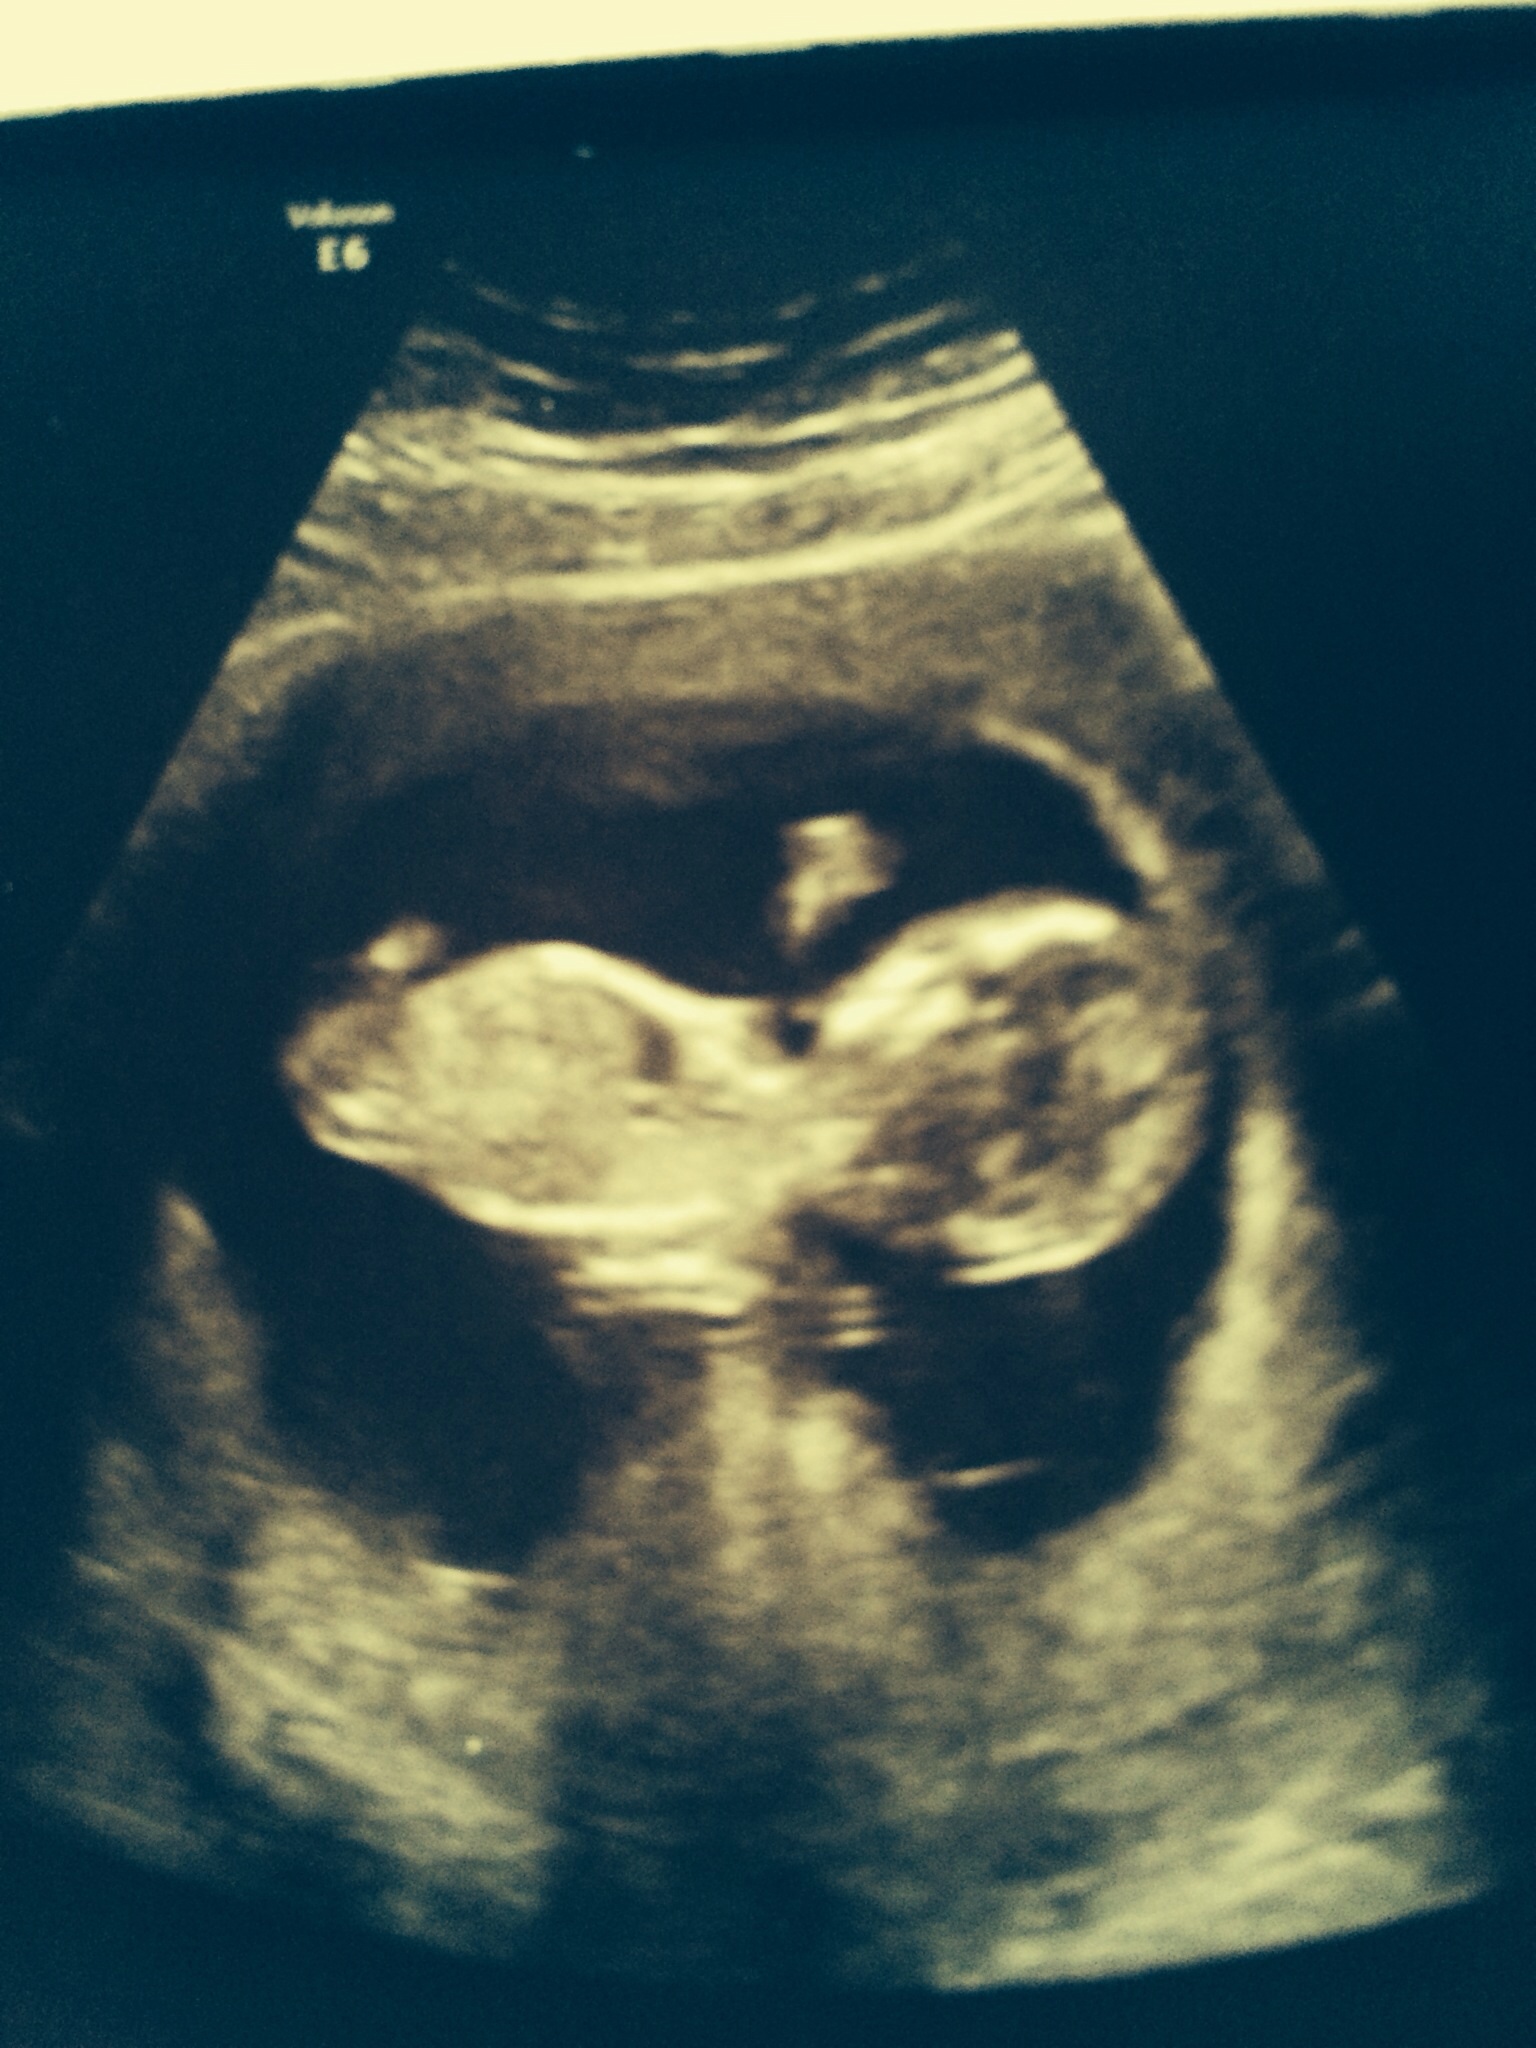

Any nub guesses? Not sure if baby is in correct position? I'm 13w 5 days xx

Baby is turned too much. Looking at its back with this view.

I'm not seeing a nub in this shot. Do you have any others?